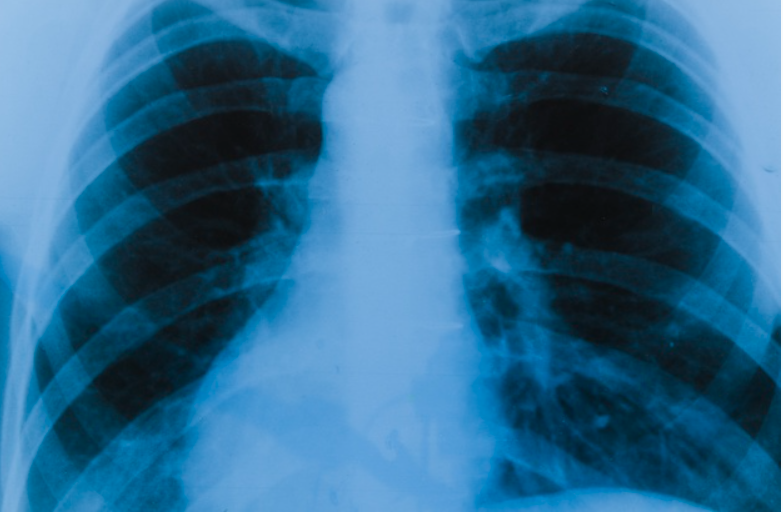

Certifican nuevamente a ESCI como centro de detección de cáncer de pulmón

El Señorial Centro de Imágenes volvió a ser certificado por el Colegio Americano de Radiología (ACR) como centro para detectar el cáncer de pulmón. La certificación de El Señorial Centro de Imágenes (ESCI), primer centro de detección de cáncer del pulmón en el país, se consiguió gracias a la inversión privada y al esfuerzo de manos puertorriqueñas.